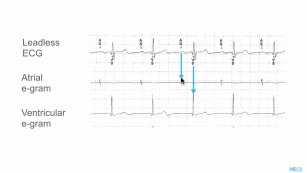

Understanding markers and annotations on an ECG. 27th Dec 2017 - Kristian Webb Learn the mystifying language of ECG markers in this video by Dr Kristian Webb.